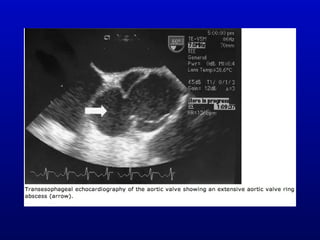

Echocardiography

• Transesophageal

– Detection of valve ring abscess (87% vs.

28% sensitivity for TTE)

Echocardiography • Transthoracic – Relativelylow sensitivity – Good specificity • Transesophageal – Detection of valve ring abscess (87% vs. 28% sensitivity for TTE) – Detection of prosthetic valve IE